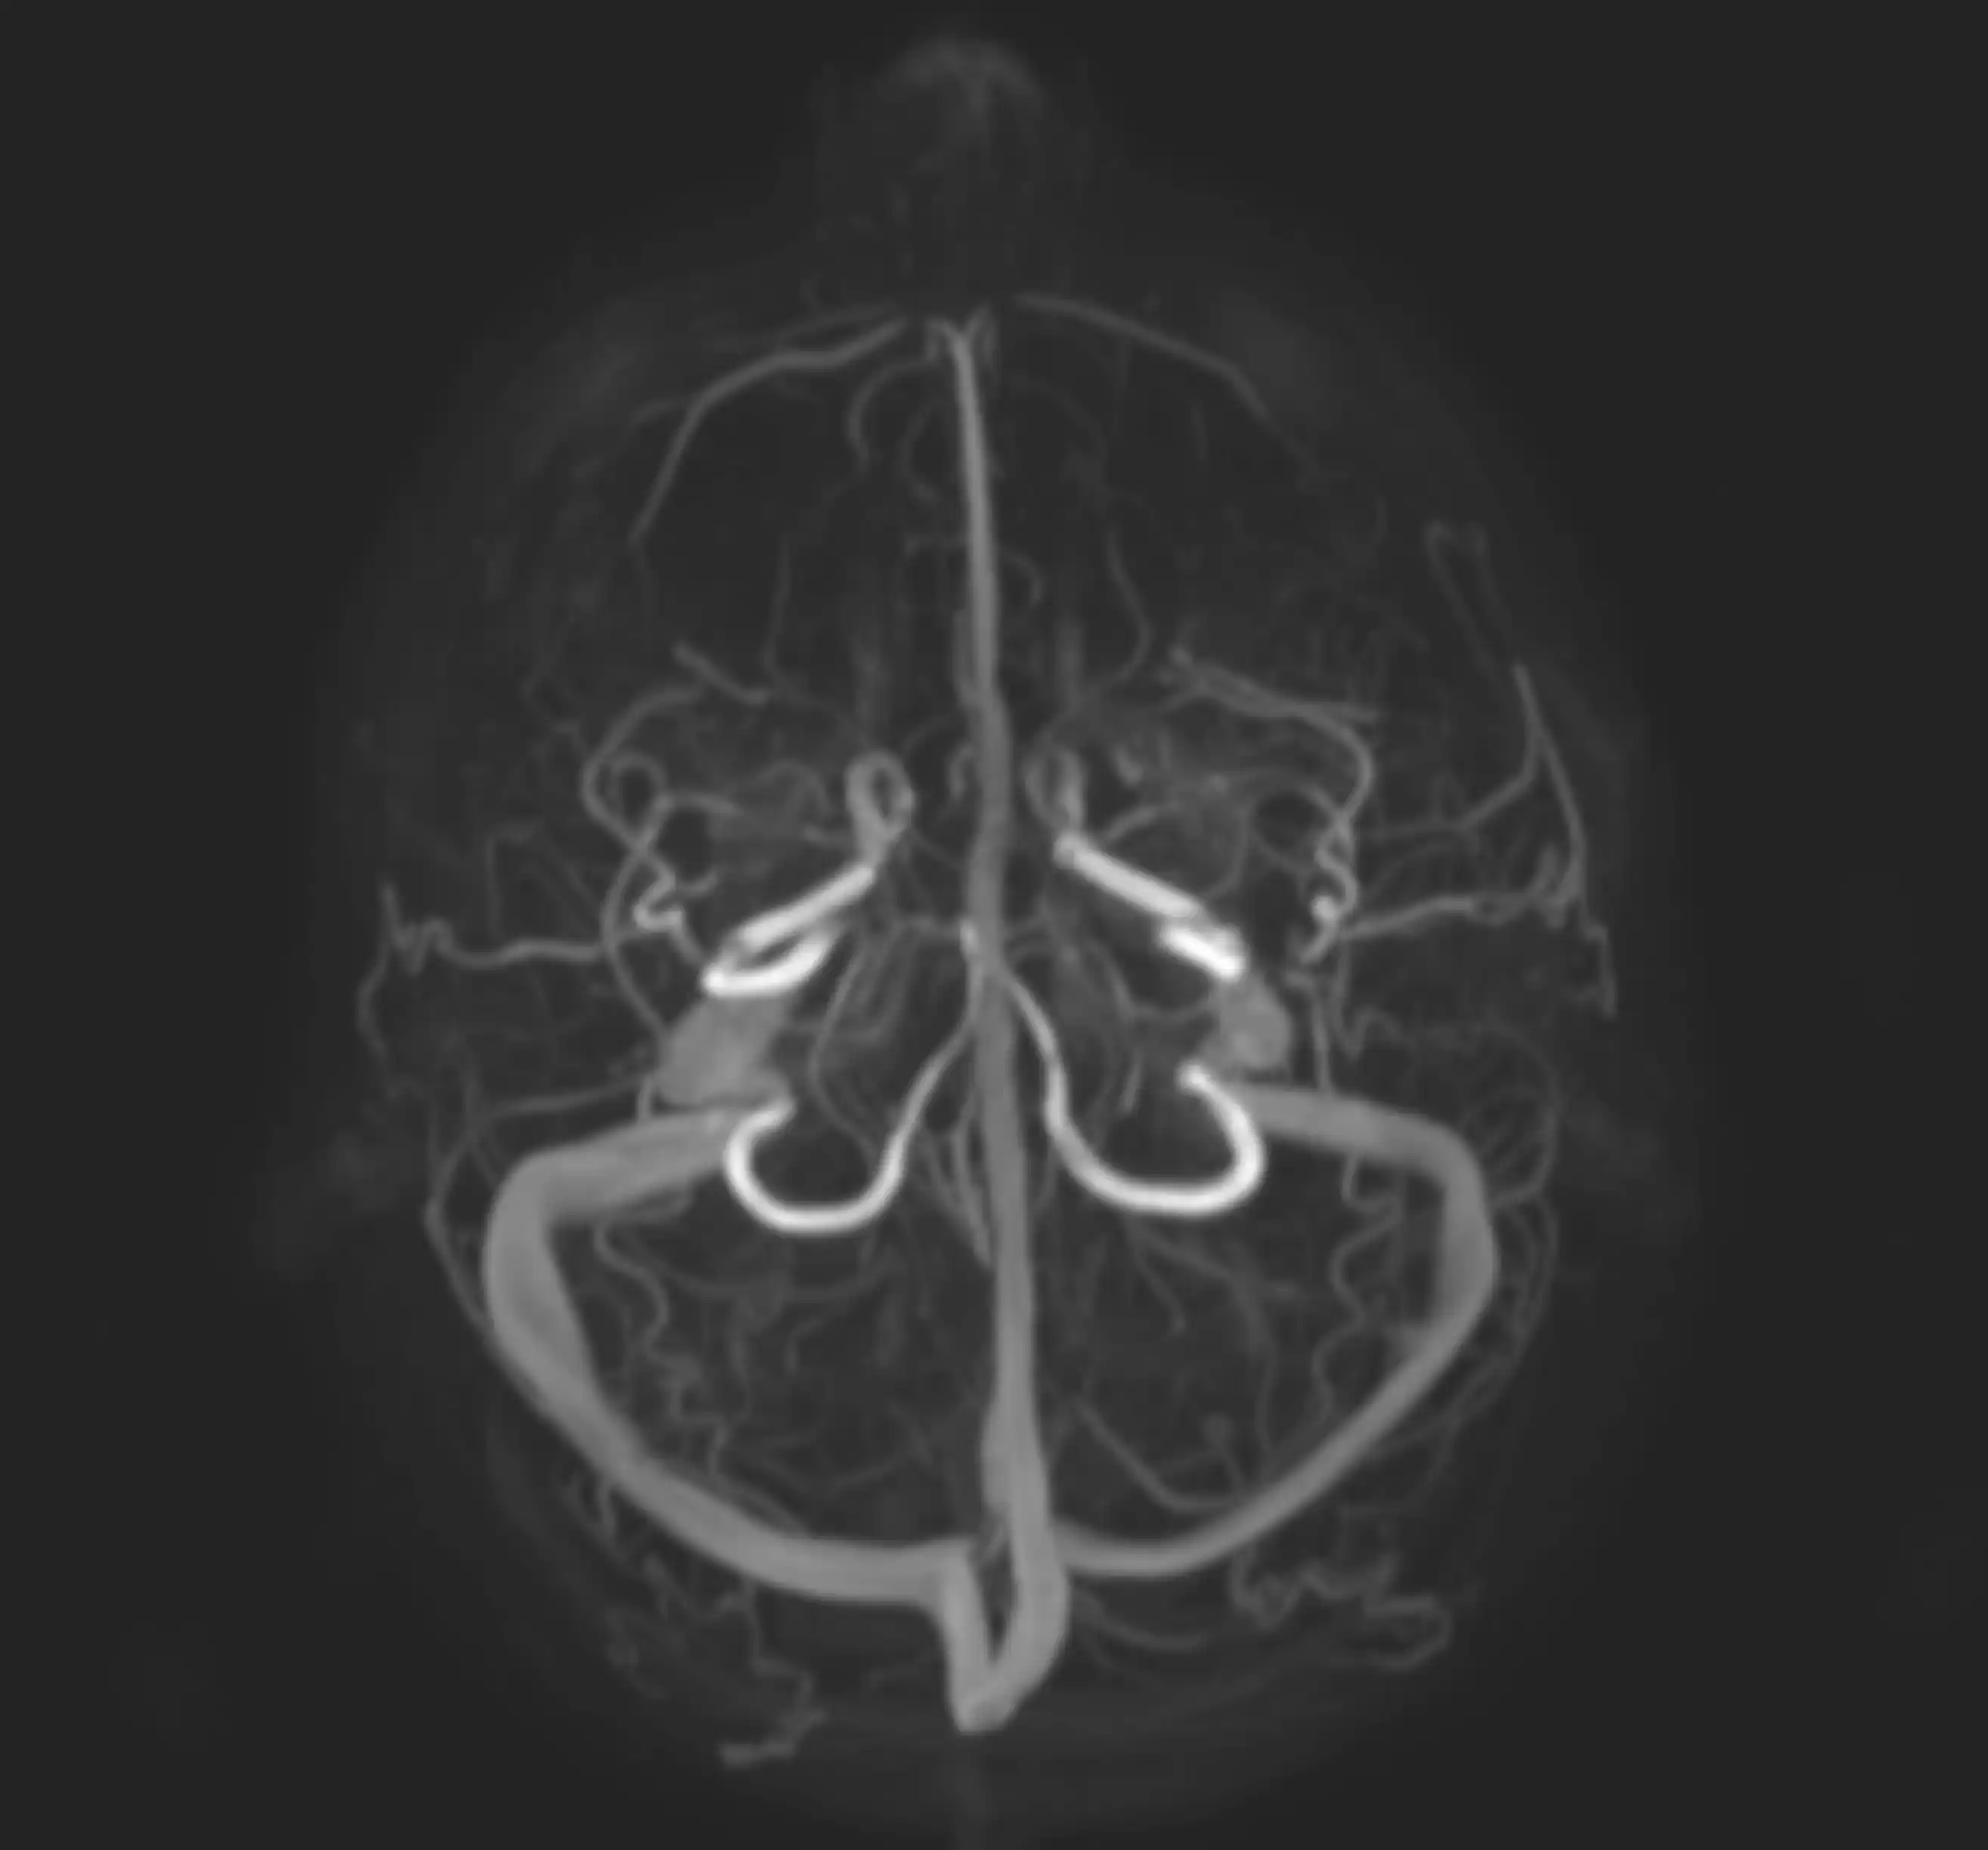

МРТ-ангіографія (МРА) — це сучасний метод дослідження судин головного мозку, шиї та інших ділянок тіла за допомогою магнітно-резонансної томографії.

Метод дозволяє оцінити стан артерій і вен без хірургічного втручання та без рентгенівського випромінювання.

Що показує МРТ-ангіографія

Обстеження дозволяє виявити:

- аневризми

- тромбози

- звуження або закупорку судин

- вроджені аномалії розвитку

- порушення кровопостачання мозку

- судинні мальформації